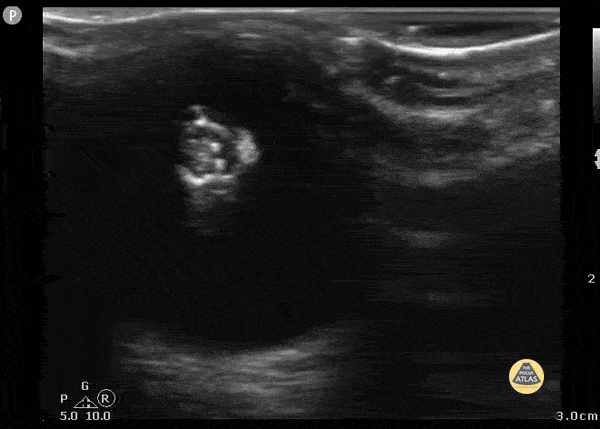

19 year old female with glaucoma presents with head trauma and abnormality of the lens on CT (calcification) that was subsequently visualized by POCUS. Contributor: Julie Leviter, MD